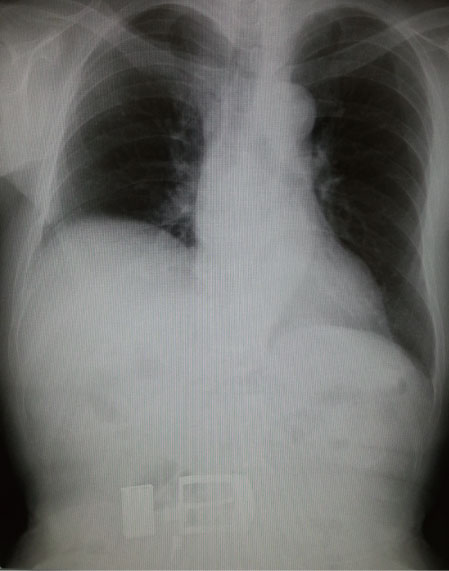

# 右横隔膜挙上

<画像所見>

・胸部Xp:右横隔膜挙上